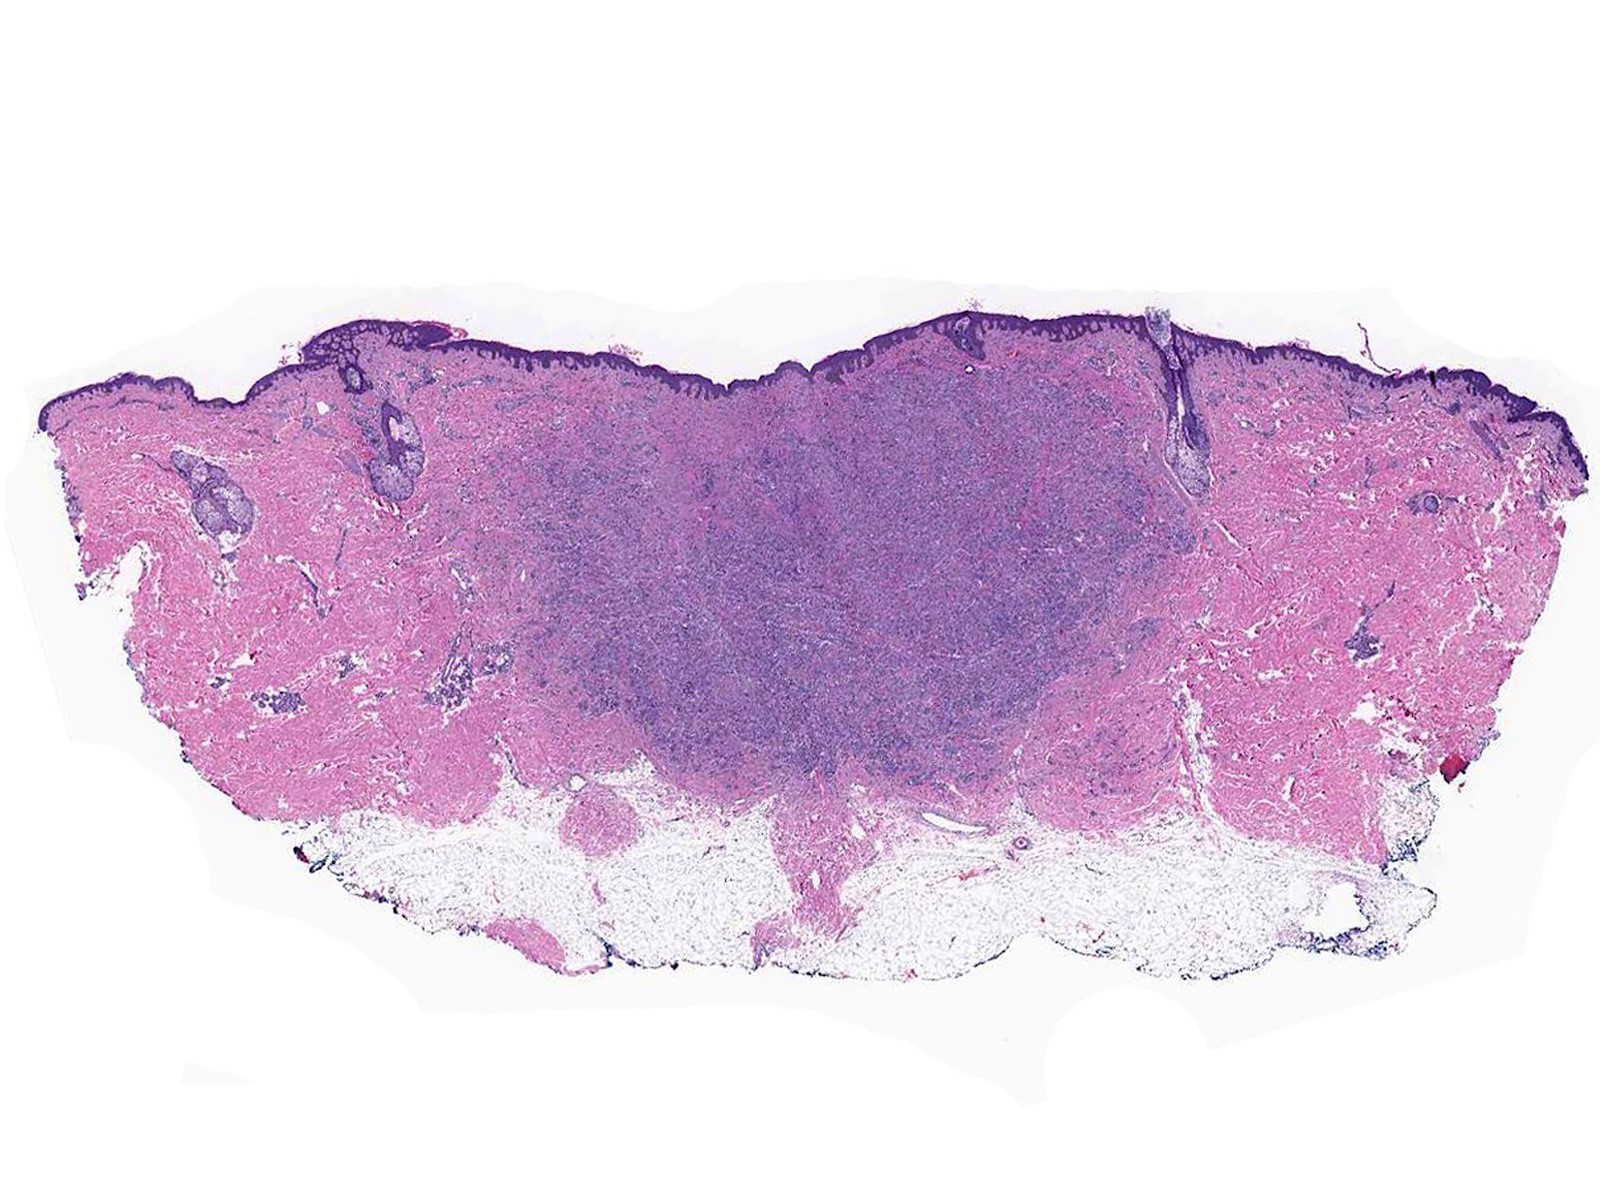

Microscopic (histologic) description

- Infiltrative or circumscribed architecture

- Can involve the subcutis

- Large polygonal cells with abundant eosinophilic granular cytoplasm and small, central nuclei

- Epidermis can show pseudocarcinomatous hyperplasia

- Lysosomal macroinclusions (pustulo-ovoid bodies of Milian) are usually present (J Cutan Pathol 2007;34:405)

- Can exhibit accentuation around arrector pili muscles or peripheral nerves (J Clin Pathol 2014;67:19)

- Nonneural granular cell tumors (S100-) can exhibit nucleomegaly, pleomorphism and variable mitotic activity (Am J Surg Pathol 1991;15:48, Histopathology 2005;47:179)

Microscopic (histologic) images

Contributed by Jarish Cohen, M.D., Ph.D.